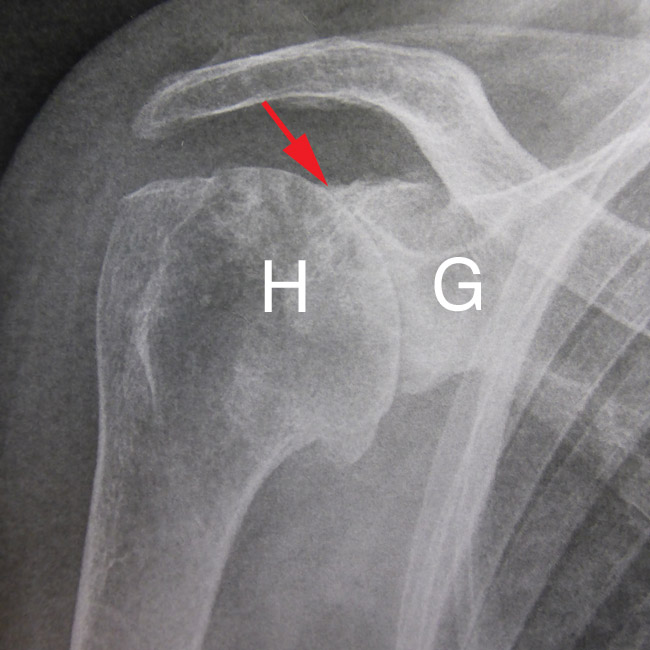

Le diagnostic se fait facilement sur de simples radiographies.

L’arthrose est le résultat de la détérioration des cartilages articulaires. Lorsque le cartilage est trop endommagé ou complètement détruit, les surfaces osseuses frottent directement l’une contre l’autre, causant la douleur et l’enlaidissement de l’articulation.

L’épaule est moins fréquemment touchée par l’arthrose que la hanche ou le genou car cette articulation ne supporte pas le poids du corps.